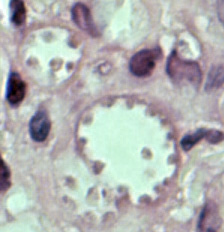

ブラジルリーシュマニア:リーシュマニア・ブラジリエンシス(Leishmania braziliensis)

中南米の森林に生息するげっ歯類、ナマケモノ、サルの皮膚のリーシュマニア症の原因虫ですが、しばしばヒトの鼻咽頭に病変を生ずることがあります。

媒介昆虫は、Psychodopygus属、Lutzomyia属のサシチョウバエです。